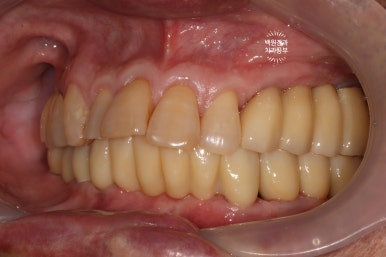

측면 사진에서도 상당히 깔끔하게 제작된 임플란트를 보실 수 있습니다!!!

최소한의 비용을 위하여 충치가 있었던 치아들은 간단히 레진으로 떼워 마무리해드렸습니다.

이렇게까지 제작해드리는데, 위턱에는 4개의 임플란트 아래턱에는 6개의 임플란트만 사용하였을 뿐입니다.

다행이라면 60대 남성분임에도 불구하고, 악궁이 작으신 편이라 12개의 치아만으로도 충분히 불편하지 않게 식사가 가능하셨습니다.